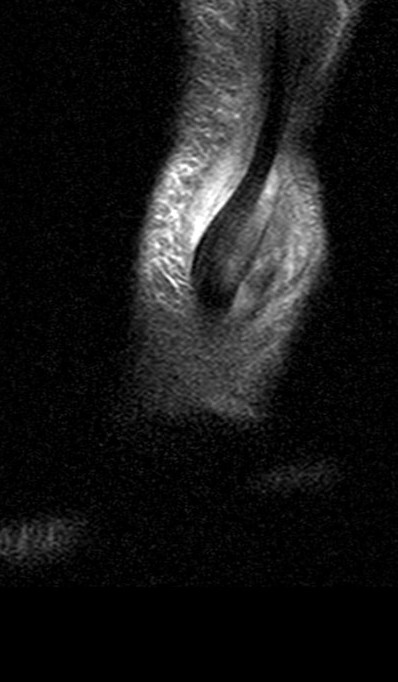

Figure 2 for case peroneal dislocation

Figure 2

Both peroneals are dislocated around fibula. Retinaculum is torn. Initial case was missed. Patient walking around for nearly a year like this.

peroneal dislocation